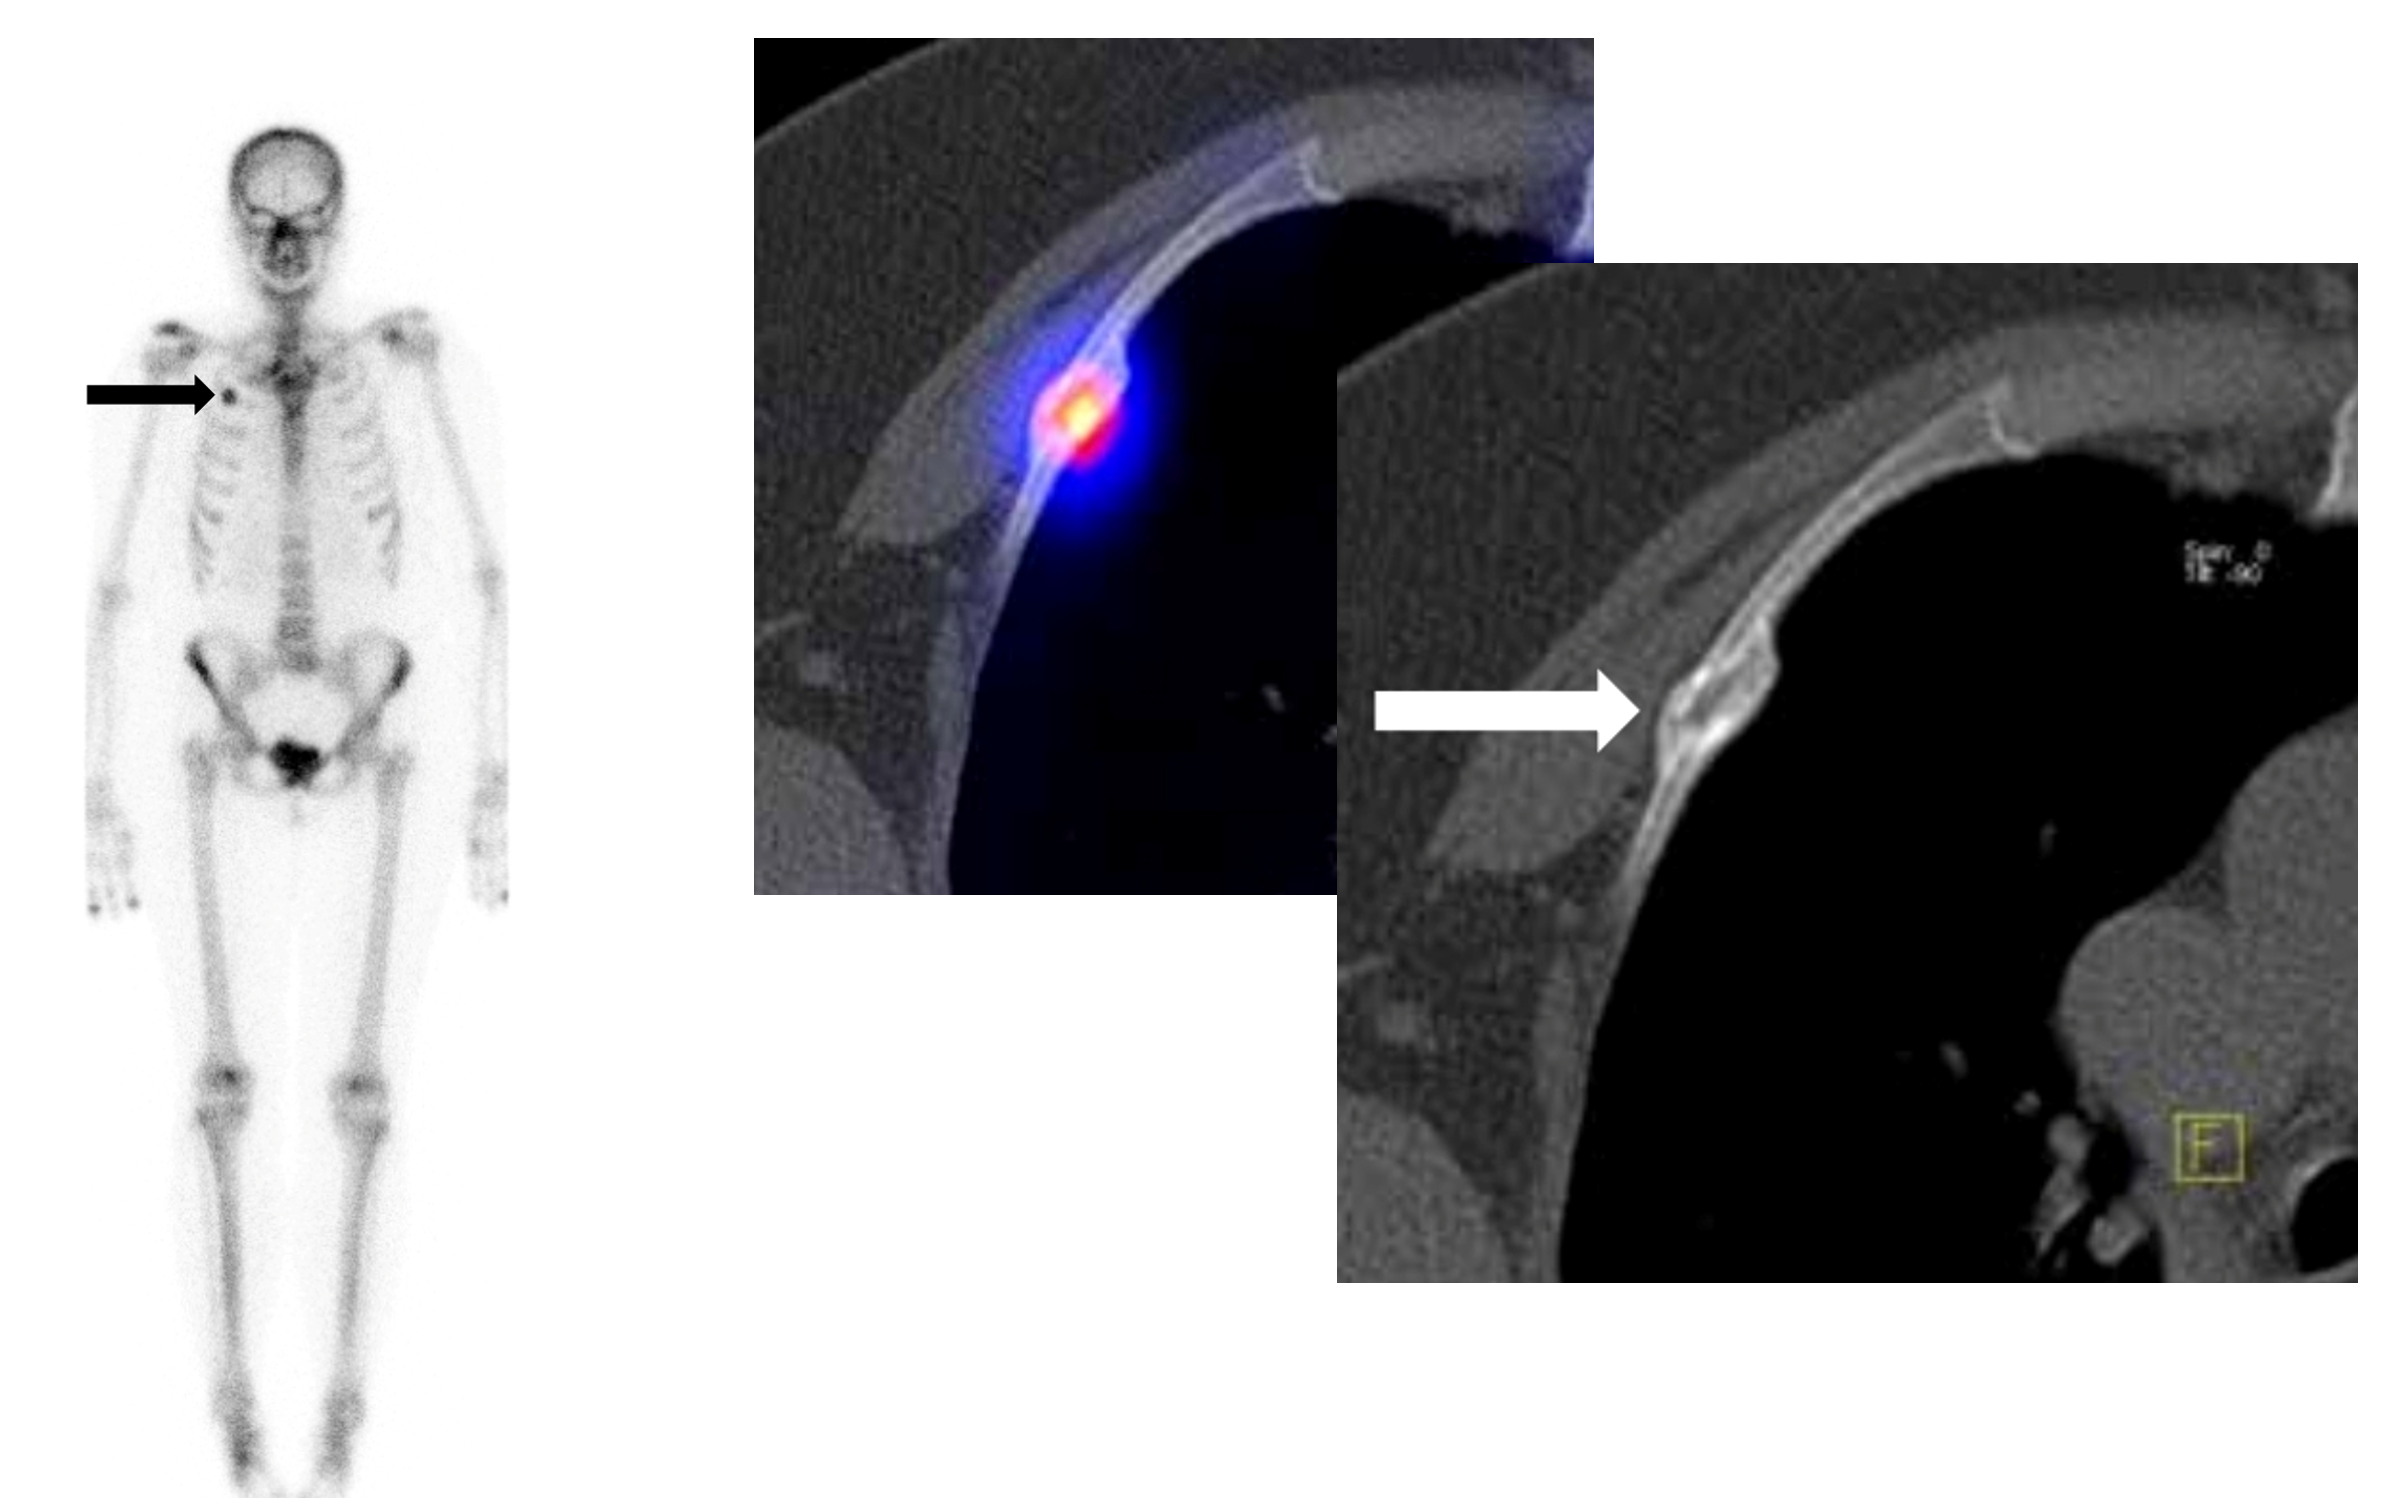

Το Lu-177 PSMA αποτελεί μια στοχευμένη ραδιονουκλιδική θεραπεία για ασθενείς με ορμονοάντοχο μεταστατικό καρκίνο του προστάτη (mCRPC), αξιοποιώντας τη υπερέκφραση του PSMA (Prostate-Specific Membrane Antigen) στα καρκινικά κύτταρα. Προηγείται PSMA PET/CT για ακριβή χαρτογράφηση της νόσου και επιβεβαίωση επαρκούς πρόσληψης του ραδιοφάρμακου. Το Lu-177 PSMA συνδέεται στους PSMA-υποδοχείς, επιτρέποντας στοχευμένη ακτινική δράση υψηλής κυτταροτοξικότητας σε μεταστατικές εστίες οστών και μαλακών μορίων. Η χρήση εξειδικευμένων δοσιμετρικών εργαλείων επιτρέπει την ποσοτική αποτίμηση της δόσης σε κρίσιμα όργανα (π.χ. σιελογόνοι αδένες, νεφροί, μυελός) και στον όγκο, συμβάλλοντας σε εξατομικευμένη θεραπευτική προσέγγιση. Μετά από κάθε κύκλο πραγματοποιείται PSMA PET/CT ή FDG PET/CT (όπου ενδείκνυται), καθώς και στενός αιματολογικός έλεγχος για αξιολόγηση της ανταπόκρισης και των πιθανών τοξικοτήτων. Η θεραπεία έχει αποδειχθεί ιδιαίτερα αποτελεσματική στη μείωση του καρκινικού φορτίου, στη βελτίωση του πόνου, στη μείωση των επιπέδων PSA και στη σημαντική παράταση του προσδόκιμου επιβίωσης σε ασθενείς με εκτεταμένη και ανθεκτική νόσο.